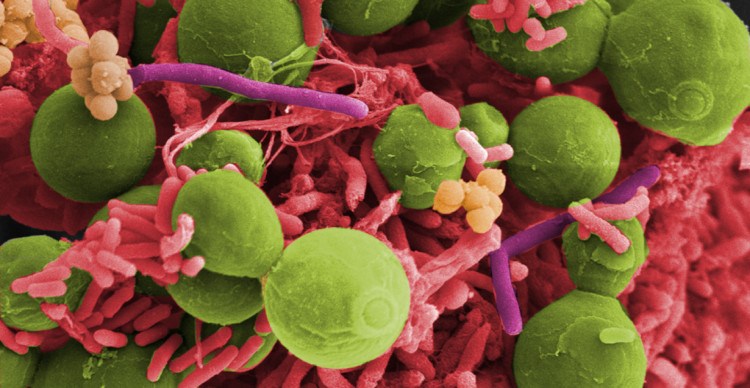

Center for Advanced Biomaterials for Health Care

Centro Interdipartimentale di Ricerca sui Biomateriali (CRIB), Napoli

Il Center for Advanced Biomaterials for Health Care (CABHC) sviluppa materiali e tecnologie per progettare piattaforme e sistemi di ispirazione biologica per applicazioni nel settore biomedico.